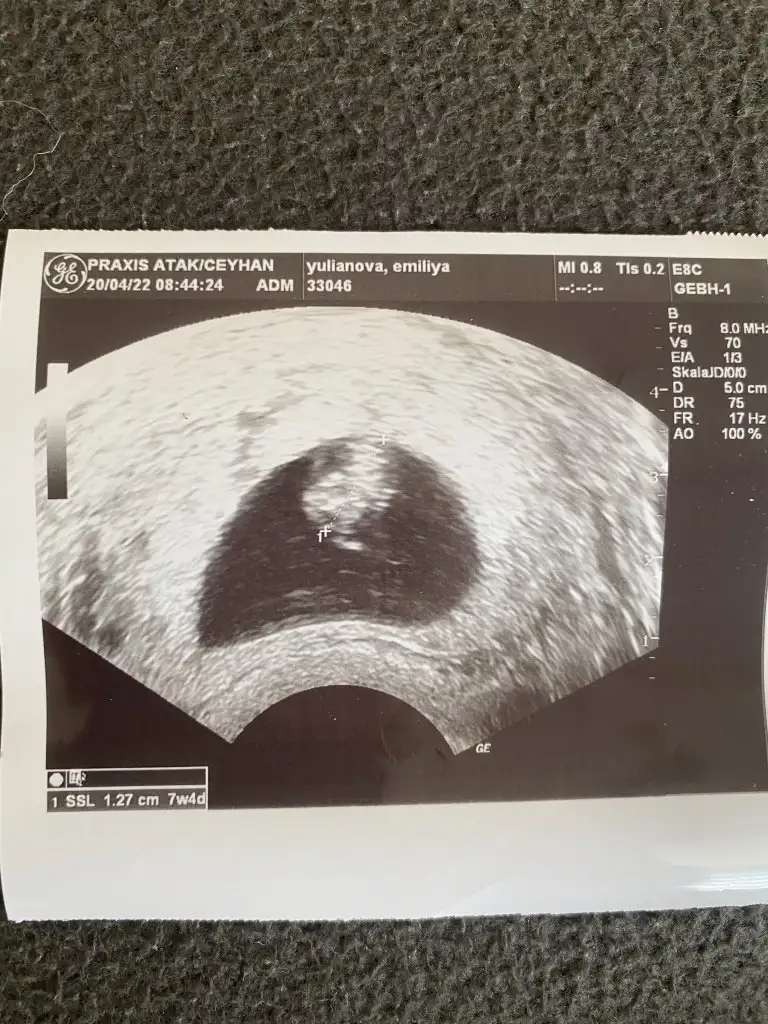

Kız bence7 hafta 4 gunluk vajinal muane ile bakildi acaba tahminde bulunabilirmisiniz.

Kız canımHanımlar bizim cinsiyetimiz nedir acaba tahmin edebilir misiniz 12 haftalik